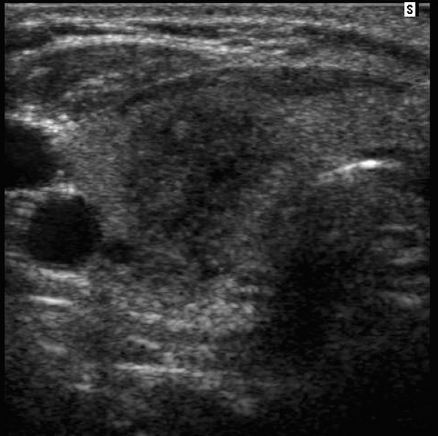

Testicular epidermoid cyst

• benign germ cell neoplasm

• monodermal teratoma - only ectodermal components

• appearance

• well-marginated lesoins that are typically hypoechoic

• hyperechoic rim with complete or partial rim of calcification

• onion ring/peel appearance